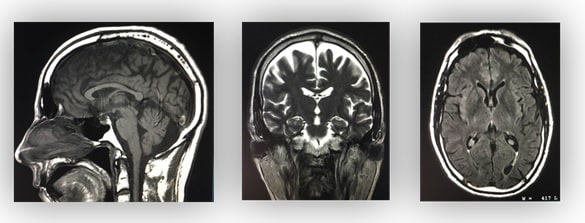

Magnetic resonance imaging (MRI) is arguably the most sophisticated imaging method used in clinical medicine. In recent years, MRI scans have become increasingly common, as costs decrease. In this article, we will outline the basic principles behind MRI scans, how to orientate and interpret a scan, and address some of their advantages and disadvantages compared to other imaging modalities. Pro Feature - 3D Model You've Discovered a Pro Feature Access our 3D Model Library Explore, cut, dissect, annotate and manipulate our 3D models to visualise anatomy in a dynamic, interactive way. Learn More Basic Principles MRI scans work as an imaging method due to the unique make-up of the human body. We are comprised entirely of cells which all contain water – principally made of hydrogen ions (H2O). The magnet embedded within the MRI scanner can act on these positively charged hydrogen ions (H+ ions) and cause them to ‘spin’ in an identical manner. By varying the strength and direction of this magnetic field, we can change the direction of ‘spin’ of the protons, enabling us to build layers of detail. When the magnet is switched off, the protons will gradually return to their original state in a process known as precession. Fundamentally, the different tissue types within the body return at different rates and it is this that allows us to visualise and differentiate between the different tissues of the body. <a href="https://pulseradeducation.com"> Pulse Radiology Education</a> Fig 1MRI scanning is based on the excitation and relaxation of protons. Uses of MRI Scanning Magnetic resonance imaging can produce highly sophisticated and highly detailed images of the human body. Generally speaking, MRI scanning is excellent for visualising soft tissue – and so it is often used in the detection of tumours, strokes and bleeds. It also can be used to visualise the functionality of suspected masses and tumours through IV, gadolinium-based agents. MRI scans have many advantages. As stated previously, they provide excellent detail of the soft tissues of the body, and they do not cause any radiation exposure to the patient. However, they are time consuming – averaging approximately 35-45 minutes to complete. This limits their use in trauma and emergency situations, where CT scanning is often preferred. They are also by far the most expensive of all the imaging modalities available. Factor CT (CT abdo used as example) MRI X-ray (CXR used as example) Ultrasound Duration 3-7 minutes 30-45 min 2-3 min 5-10 minutes Cost Cheaper Expensive Cheap Cheap Dimensions 3 3 2 2 Soft tissue Poor detail Excellent detail Poor detail Poor detail Bone Excellent detail Poor detail Excellent detail Poor detail Radiation 10mSv None 0.15mSv None At present, there are no known long lasting adverse effects from MRI scans. However, MRI safety has recently become a major focus in hospital and outpatient environments due to the potential attraction to ferromagnetic objects and devices. Some medical and implantable devices are considered contraindications for MRI evaluation – such as cardiac pacemakers, heart monitors, defibrillators and other battery-operated devices. Interpreting a MRI Scan Image View MRI scans, much like computed tomography, typically produce three anatomical views; sagittal, coronal and axial (similar to the planes of the body). When interpreting axial views, it is important to appreciate that the image is viewed from the feet upwards – and so the left-hand side of the image refers to the patient’s right (and vice versa). <a href="https://pulseradeducation.com"> Pulse Radiology Education</a> Fig 2The three main views obtained when MRI scanning. Left to right: Sagittal, coronal and axial. Image Weight Once the view of the scan has been determined, the second step is to work out the weight of the image. The magnetic fields produced by the scanner can be manipulated to produce two distinct types of image – T1 weighted and T2 weighted. The resulting images will show different tissue types in different densities: Appearance T1 Weighted Image T2 Weighted Image White Fat Protein Rich Fluid Water Content E.g. Inflammation, Tumour, Haemorrhage, Infection Intermediate Gray Spinal Matter darker than White White Spinal matter darker than gray spinal matter. Dark Bone Air Water Content e.g. Inflamation, Tumour, Haemorrhage Bone Air Fat Note: It can help to remember that a T tWo weighted image shows Water as White. Clinical Relevance Spinal Cord Compression Magnetic resonance imaging can be used to assess the extent of cord compression, when there is a suspicion of stenosis, disc herniation or cauda equina. The figure below shows a T2 weighted, sagittal MRI of the lumbar spine. The thecal sac is easily visible as the 1cm thick white band running posterior to the vertebral bodies. This is interupted at the L4/L5 level by a small round dark area, which is the herniation of the intervertebral disc into the central canal. By TeachMeSeries Ltd (2025) Fig 3Sagittal plane T2 weighted MRI Scan of lumbar spine, demonstrating disc herniation at L4/5 level. Do you think you’re ready? Take the quiz below Pro Feature - Quiz Magnetic Resonance Imaging (MRI) Scanning Question 1 of 2 Submitting... Skip Next Rate question: You scored 0% Skipped: 0/2 1800 More Questions Available Upgrade to TeachMeAnatomy Pro Challenge yourself with over 1800 multiple-choice questions to reinforce learning Learn More Rate This Article